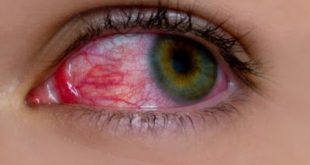

Αξίζει να σημειωθεί ότι η ταχεία βιοψία απαγορεύεται αυστηρώς σε περιπτώσεις μελαγχρωστικών αλλοιώσεων λόγω εξαντλήσεως του ιστού στον οποίο πιθανότατα να αντιπροσωπεύονται οι παράμετροι προγνωστικής αξίας του μελανώματος(πχ βάθος ανάπτυξης κατά Breslow). To ίδιο ισχύει και σε υλικό λεμφαδένα φρουρού σε ασθενείς με μελάνωμα. Υπάρχουν όμως περιπτώσεις όπου ο Παθολογοανατόμος δεν μπορεί να αποφασίσει για την διάγνωση της Τ.Β. και για τον λόγο αυτό πρέπει να επισημαίνει στο χειρουργό ότι, αν και ο ιστός είναι αντιπροσωπευτικός, για την οριστική διάγνωση είναι απαραίτητη η αναμονή των τομών παραφίνης.